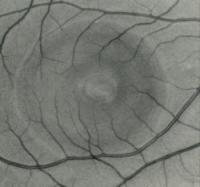

chriorétinopathie sereuse centrale

crsc1.jpg